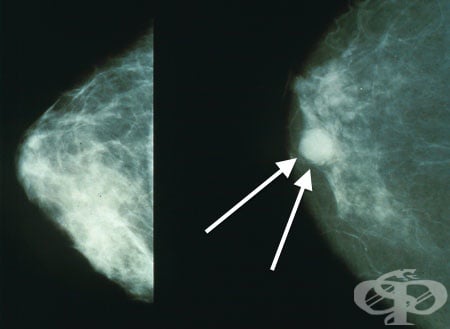

8.1. Бучка или нова маса в гърдите

Бучката, която представлява окръглено плътно, възловидно образувание, е първият признак, говорещ за наличен рак на гърдата. Бучката може да бъде разположена във всяка една част на гърдата, но най-честата локализация на тумора е горният външен квадрант на жлезата.

Бучката обикновено е единична и се усеща като различна тъкан от останалата структура на гърдата. Образуванието може да бъде както спонтанно болезнено, така и при опипване. Повече от 80% от случаите на рак на гърдата са диагностицирани, когато жената си е открила „бучка”.